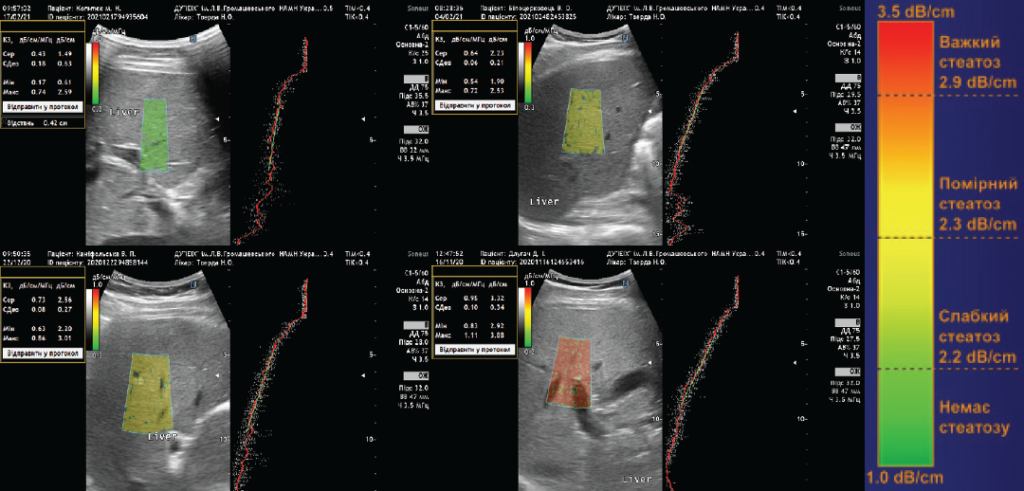

Ультразвукова стеатометрія — інформативний метод для скринінгу неалкогольної жирової хвороби печінки при мінімально і максимально вираженому стеатозі.

Стеатоз підступно переходить у стеатогепатит і призводить до термінальних форм ураження печінки: цирозу,  ГЦК та портальної гіпертензії. Хвороба вражає до 10-15% худих людей. Точних специфічних біохімічних тестів НАЖХП не існує. Така підступність НАЖХП потребує розробки концепції обстеження за допомогою ультразвукового (УЗ) скринінгу.

Для визначення вираженості стеатозу використовується шкала (дБ/см), яка корелює зі ступенем стеатозу за даними біопсії печінки.

NAS (NAFLD activity score — шкала активності неалкогольної жирової хвороби печінки):

S0 — немає стеатозу: < 2, 19 дБ/см;

S1 — мінімальний стеатоз: < 5% гепатоцитів зі стеатозом; 2,2–2,29 дБ/см;

S2 — помірний стеатоз: < 6–32% гепатоцитів зі стеатозом; 2,3–2,9 дБ/см;

S3 — виражений стеатоз: < 33–100% гепатоцитів зі стеатозом;

> 2,9 дБ/см.

Саме  інноваційні УЗ технології еластографії і стеатометрії дозволяють неінвазивно, аналогічно процедурі простого УЗД, визначити стадію фіброзу/цирозу і стеатозу, а також з’ясувати тяжкість перебігу і прогноз захворювання.